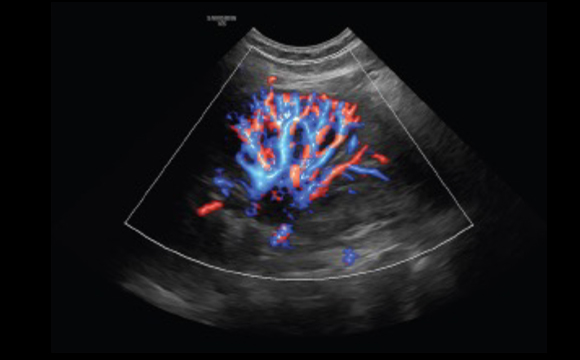

Visualisierung des langsamen Flusses in mikrovaskulären Strukturen

MV-Flow™ bietet Ihnen eine Alternative zum Powerdoppler zur Visualisierung von langsamen Flüssen. Hohe Bildraten und fortschrittliche Filtertechnologien ermöglichen eine detaillierte Ansicht des Blutflusses in Relation zum umgebenden Gewebe oder der Pathologie, in einer angepassten räumlichen und zeitlichen Auflösung.

Milz mit MV-Flow™ ³

Anzeige des Blutflusses in einer 3D-ähnlichen Darstellung

LumiFlow™ bietet eine plastische Darstellung des Blutflusses und mikrovaskulärer Strukturen. Diese intuitive dreidimensionale Visualisierung ermöglicht die Differenzierung eng benachbarter Gefäße.

Niere S-Flow™ mit LumiFlow™